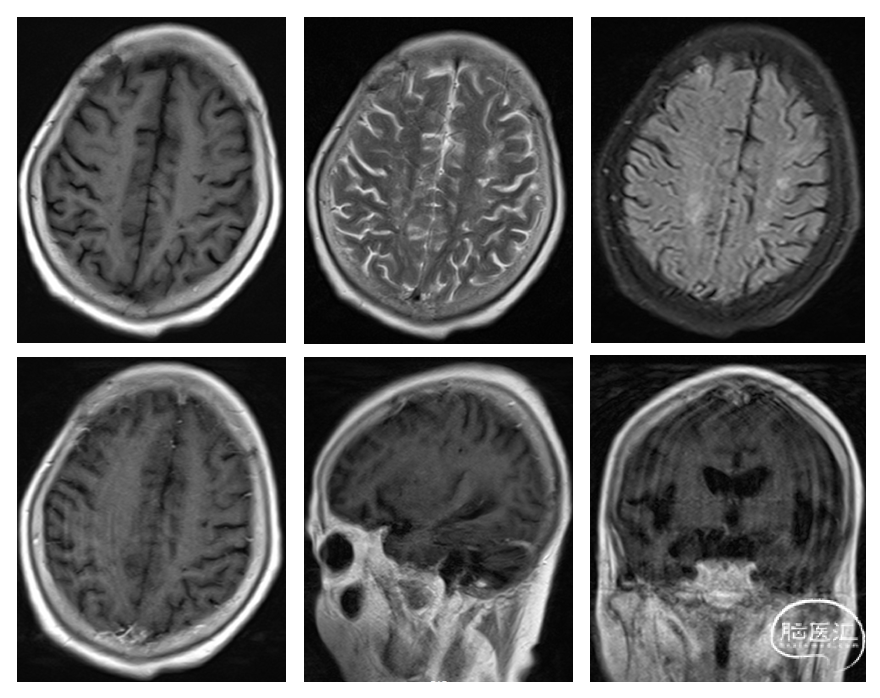

手术1月后患者至血液内科进一步化疗,按照R-MTX(利妥昔单抗0.6g d0,MTX 6.2g d1)方案进行化疗1次,接着按照R-CHOP+MTX方案(汉利康600mg d0,MTX 6.2g d1,环磷酰胺1.3g d3,盖诺40mg d3,立幸50mg d3, 地塞米松15mg d3-7)化疗3次。化疗过程顺利,患者反应迟钝及走路不稳症状较前有所改善,复查头颅MRI提示颅内病灶较前缩小(图3)。恢复顺利后出院。出院后患者未定期随访,于2024年2月出现病情恶化,抢救无效死亡。